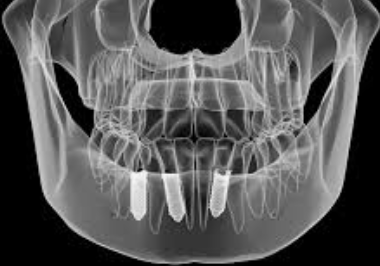

임플란트 뼈이식 절차 전에 치과 전문가는 구강 및 전반적인 건강 상태를 철저히 검사합니다. 여기에는 턱뼈의 질과 양을 평가하기 위한 육안 검사, 촉진 및 X-레이 또는 CT 스캔과 같은 진단 영상이 포함될 수 있습니다. 치과의사는 뼈 이식의 필요성, 권장 이식 유형, 수술 중 및 수술 후에 기대할 수 있는 사항을 설명하면서 절차에 대해 자세히 논의할 것입니다. 궁금하신 점은 이 때 모두 물어보면 좋습니다.

임플란트 뼈이식으로 뼈재생이 충분히 이루어졌음을 치과의사가 방사선 사진을 통해 확인하면 임플란트 식립을 진행할 수 있습니다.